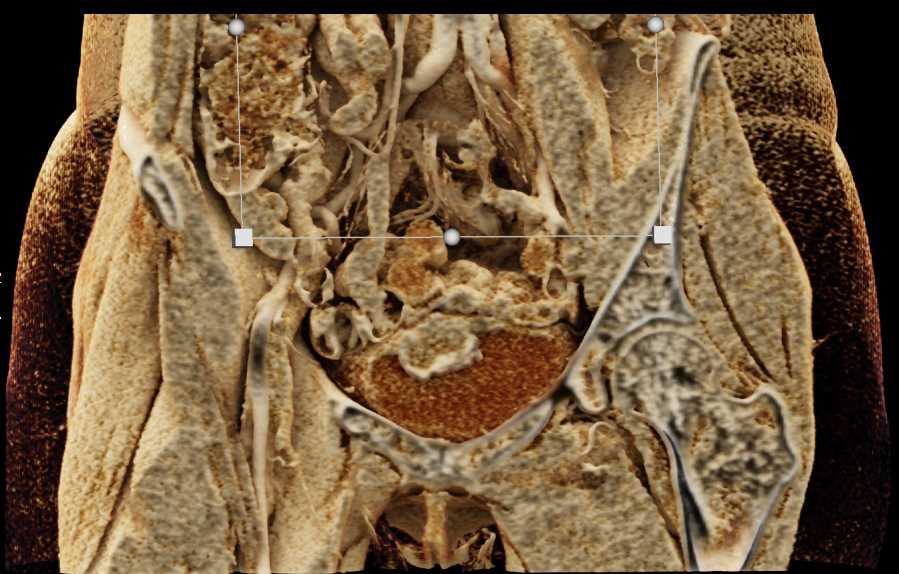

Urachal Carcinoma of the Bladder